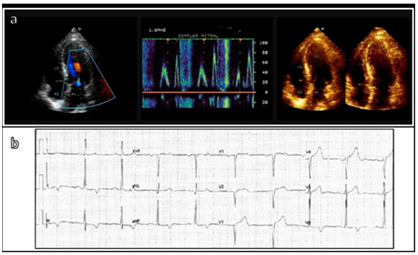

65-year-old male patient with a history of systemic arterial hypertension; diagnosis of asymmetric HOCM of 3 years of evolution described by echocardiography as LV hypertrophy with a basal distribution, septum width of 18 mm, LVOT maximum gradient of 55 mm Hg at rest, LVEF 75%; managed with ACE inhibitor and beta-blockers. He was seen in consultation due to symptoms of dyspnea, palpitations and progressive angina, NYHA functional class II-III. A new transthoracic echocardiogram was performed with LVOT obstructive gradient of 65 mmHg (Figure 1), 21 mm septum with, LVEF 76%, moderate dilation of left atrium, PASP 32 mm Hg; EKG Sokolow-Lyon index 35 mm. Dobutamine stress echocardiogram was performed with dynamic obstructive gradient of 257 mm Hg, moderate-severe systolic anterior motion (SAM) of mitral valve. Next, cardiac catheterization and ventriculography were performed observing coronary arteries without significant lesions and adequate diameter of septal branches, severely hypertrophied LV with LVEF 80% and end-diastolic pressure of 16 mm Hg. We decided to perform ASA.

Figure 1 A) TT echocardiogram, B) Electrocardiogram with systolic overload.